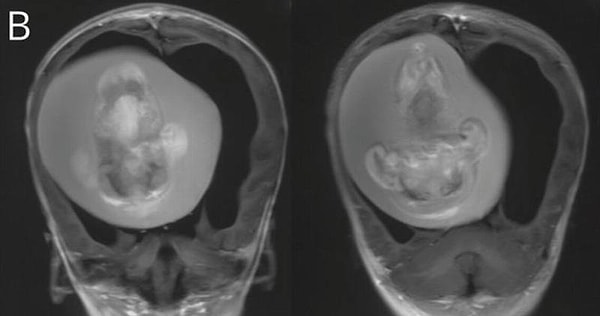

Как только МРТ показала существование близнеца, который давил на ее мозг, врачи поняли, что плод нужно немедленно удалить. К тому времени, как они смогли извлечь его, близнец уже несколько месяцев рос внутри черепа малышки — у него развились кости, органы и конечности.

Этот случай был тщательно изучен и опубликован в виде истории в журнале Neurology.

Доктор Цзунцзе Ли, невролог из больницы Хуашань, который лечил девочку, рассказал: «Предполагается, что внутричерепной плод-в-плоде возникает из неразделенных бластоцист. Соединенные части развиваются в передний мозг плода-хозяина и обволакивают другой эмбрион во время роста нервной пластинки».